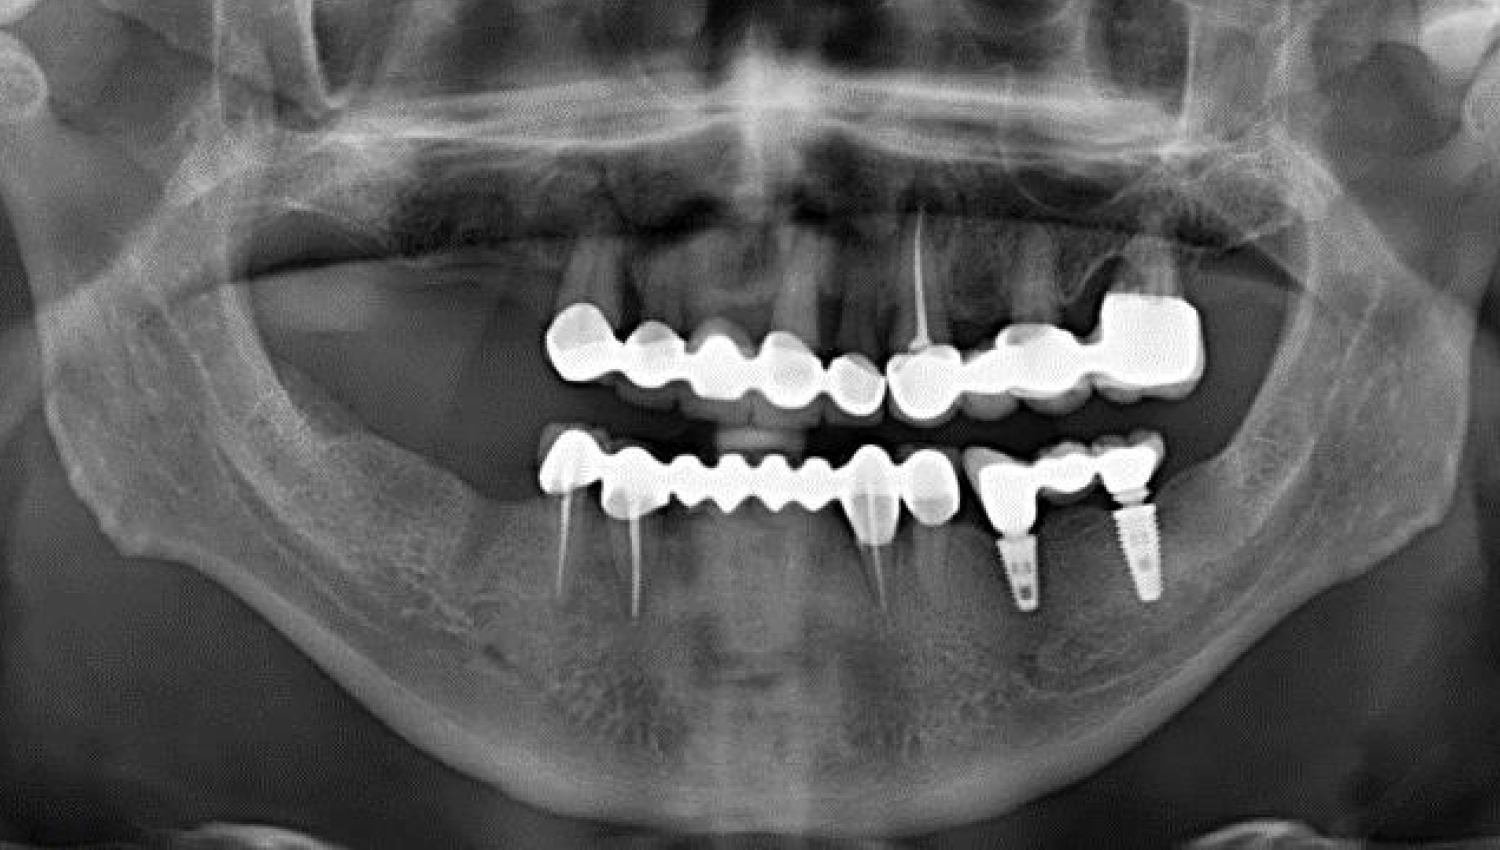

1.Initial radiological view.